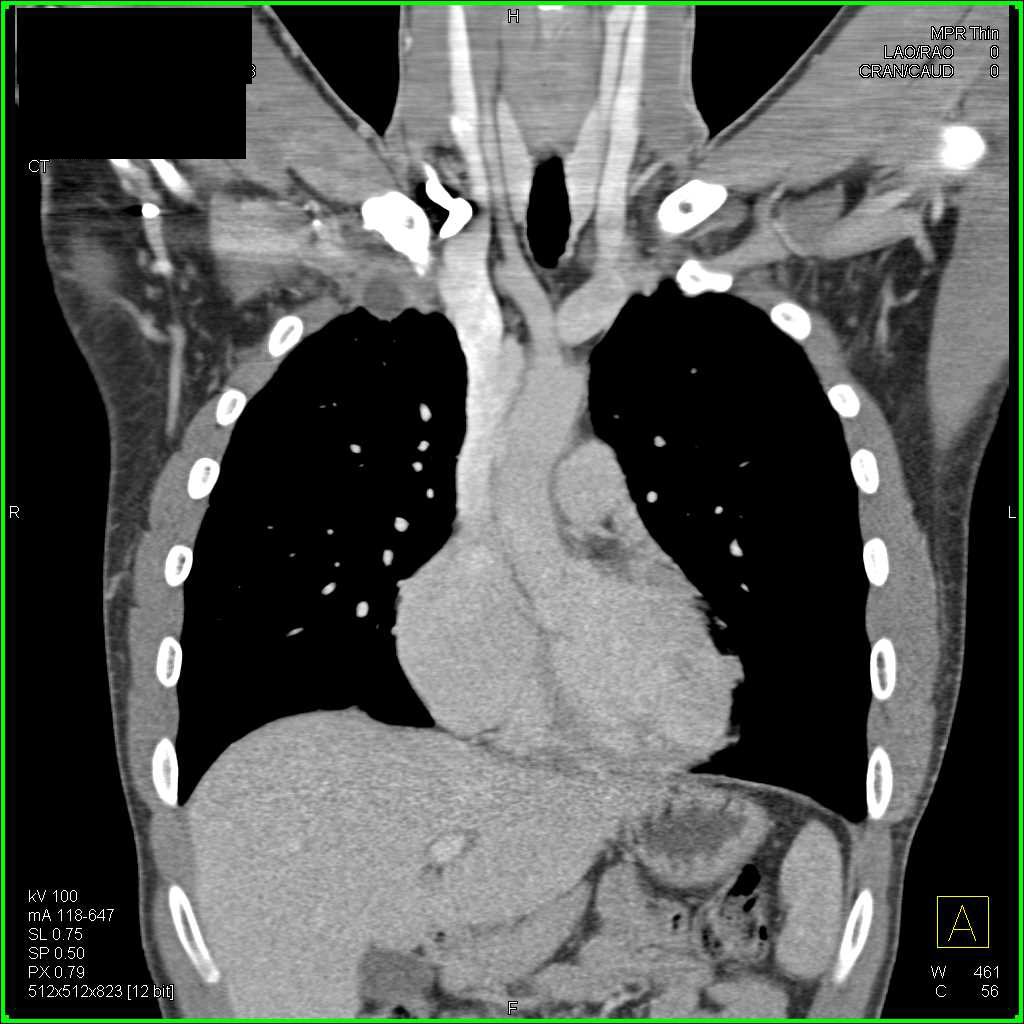

From www.ctisus.com

Abscess Right Chest Wall Extends into Muscle and Vascularity Chest What Is A Chest Wall Abscess A lung abscess is usually caused by bacteria that normally live in the mouth and are inhaled into the lungs. Abscess abuts the chest wall with a broad area of contact that causes adhesion to the chest wall (this making it more likely that tube. Aspiration of gastric contents is the. A lung abscess can be serious if left untreated,. What Is A Chest Wall Abscess.

Abscess Right Chest Wall Extends into Muscle and Vascularity Chest What Is A Chest Wall Abscess Abscess abuts the chest wall with a broad area of contact that causes adhesion to the chest wall (this making it more likely that tube. The infection causes lung tissue to die. Symptoms include fatigue, loss of appetite,. A lung abscess can be serious if left untreated, leading to complications such as bleeding in the lungs or a stroke. A. What Is A Chest Wall Abscess.